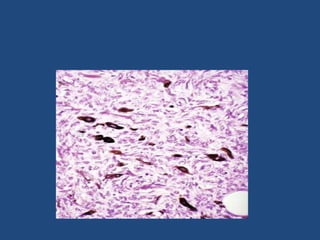

Fibrosarcomas

Common tumors of adults, although they can

occur in any age group and even be present as

congenital neoplasms.

Fibrosarcomas can arise from superficial and deep

connective tissues such as fascia, tendon,

periosteum, and scar; grow slowly or rapidly; and

often appear well circumscribed.

They usually are soft and cellular and may contain

areas of necrosis and hemorrhage

• Microscopic- The cells are arranged in fascicles

that intersect each other at acute angles,

resulting in a herringbone appearance.

• The individual cells resemble normal

fibroblasts, and a reticulin stain demonstrates

abundant fibers wrapped around each cell.

• It should be differented from monophasic

synovial sarcoma, liposarcoma, malignant

fibrous histiocytoma, and MPNST.

• Immunohistochemically the prototypical

fibrosarcoma should have reactivity for

vimentin and type I collagen but not for

smooth muscle markers, histiocytic markers,

or basal lamina components

Fibrosarcoma